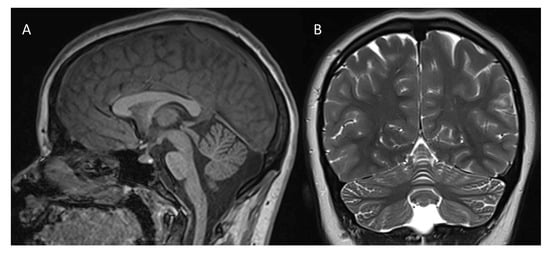

2. Case Description

2.1. Clinical Report